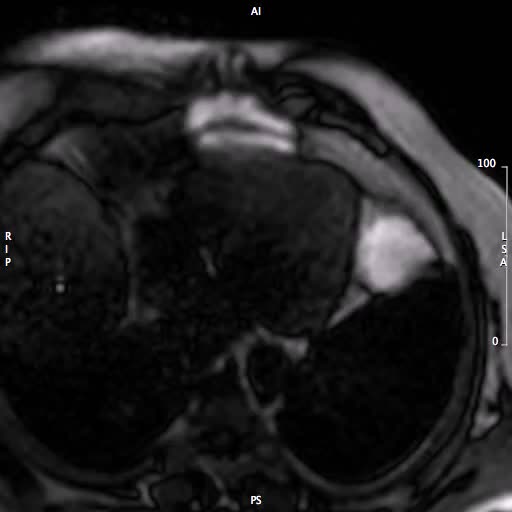

La Risonanza Magnetica nella diagnosi della stenosi aorticaAutore: Alberto Roghi